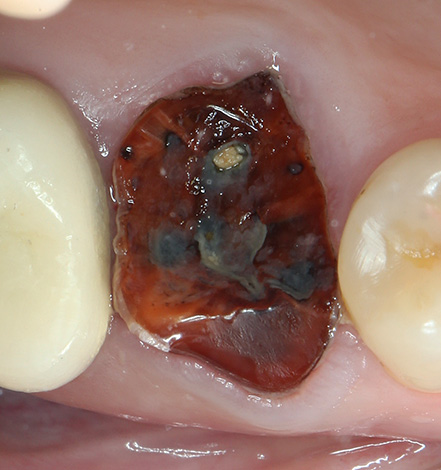

- L'opzione opposta: ci sono stati problemi con l'eruzione del dente del giudizio, cioè stiamo parlando del cosiddetto dente del giudizio retinato (nascosto nella mascella sotto la gomma), o circa semi-penetrato (parzialmente sfondando la gengiva, a volte con la formazione del cappuccio gengivale). Spesso è difficile rimuovere i denti del giudizio inferiori ed è relativamente costoso. Tuttavia, la rimozione di altri molari (sei, sette) sulla mascella inferiore non è sempre facile;

Foto di un dente semi-artificiale di saggezza:

Denti drogati - cioè spostati e situati al di fuori della loro normale posizione nella dentatura. La loro rimozione è di ulteriore complessità nel caso in cui i denti sani adiacenti diventino un ostacolo. Spesso non è possibile afferrare un dente distaccato con una pinza, quindi è necessario compiere molti sforzi per rendere la procedura chirurgica sicura per i denti normali.

I denti trattenuti si trovano completamente sotto la gengiva o si trovano generalmente nel tessuto osseo: la loro rimozione ha sempre una maggiore categoria di complessità. È più facile e veloce rimuovere il dente che è nascosto solo dalla gomma, poiché in questo caso potrebbe non essere necessario ritagliarlo dall'osso e con l'aiuto degli elevatori è possibile staccare rapidamente dal foro.

Ma la rimozione di un dente ritardato, situato in profondità nell'osso mascellare, richiede quasi sempre molto tempo (da 30-40 minuti a 2-3 ore) e richiede abilità speciali e una grande esperienza dal dentista.Pertanto, il costo della rimozione di denti complessi e raffinati raggiunge in cliniche private fino a 25 mila rubli (anche se, naturalmente, non è difficile trovare lo stesso servizio del valore di circa 5 mila se lo si desidera).